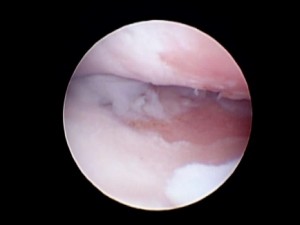

Outerbridge grade IV αλλοιώσεις στην άρθρωση του αγκώνα

Με τη μέθοδο της αρθροσκόπησης επιτρέπεται η πλήρης εξέταση των αρθρώσεων (αρθρικού χόνδρου και ενδοαρθρικών ανατομικών στοιχείων), οι οποίες απεικονίζονται με ιδιαίτερα υψηλή ευκρίνεια. Θεωρητικά, ο αρθροσκοπικός έλεγχος μπορεί να πραγματοποιηθεί σε όλες τις μεγάλες αρθρώσεις των μικρών ζώων.

• Εμπεριστατωμένη επισκόπηση της άρθρωσης λόγω της μεγεθυμένης εικόνας της αρθρικής επιφάνειας καθώς και των στοιχείων αυτής.

• Επισκόπηση δυσπρόσιτων περιοχών της άρθρωσης .